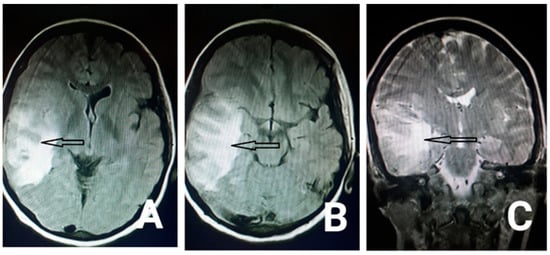

2. Case Presentation